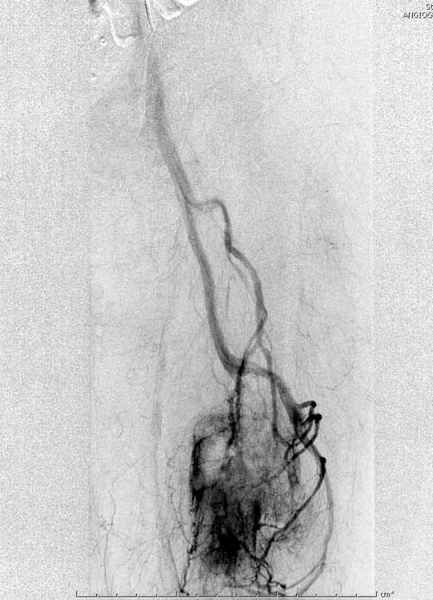

В зависимости от характера опухоли некоторые патологические переломы имеют риск кровотечения во время операции. Множественные литературные данные подтверждают, что надо проявить осторожность при интрамедуллярном остеосинтезе при неизвестных опухолях, особенно где имеется подозрение на Renal Cell Carcinoma. (RCC- hypernephroma) http://www.bonetumor.org/tumors/pages/page64.html

Со слов, больная ничем не болела, только последние 3 месяцев чувствовала боли в бедренной области. КТ брюшной полости подтвердил увеличенную правую почку. (5-6)

Для предупреждения кровотечения во время рассверливания, за день до операции провели эмболизацию сосудов питающий метастаз. http://radiology.rsnajnls.org/cgi/reprint/150/3/673.pdf (7-11, 12-15-16)